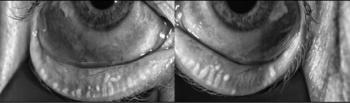

Patients deserve to have their tear film stabilized before surgery so their vision will be optimized after surgery.

Failure to address problems with the tear film and ocular surface before surgery can negatively affect surgical outcomes and patient satisfaction.

IPL’s mechanism of action a useful tool in treating underlying causes of chalazia, according to Laura M. Periman, MD.